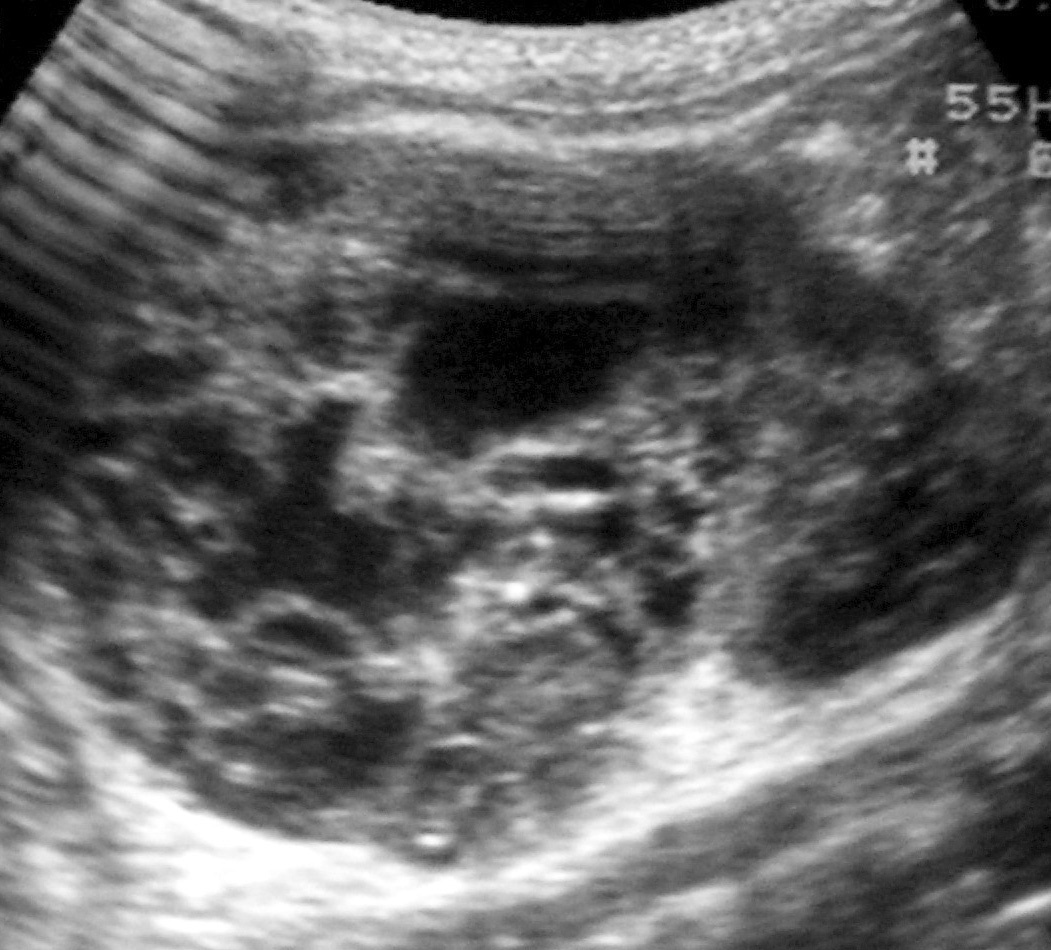

De los 11 nefromas mesoblásticos (con edad y presentación mostrados en la tabla 1) en 7 pacientes el tumor fue sólido y en 4 quístico, con presencia de un polo sólido. En 5 pacientes se encontraron áreas compatibles con necrosis, en dos sangrado intracavitario y en uno función excretora dentro de la masa. Siete pacientes tenían una colección subcapsular y 5 un anillo ecogénico periférico en la ecografía (figs. 1 y 2).

Fig. 1. Nefroma mesoblástico. Niño de 5 meses con masa abdominal palpable. (A) Ecografía abdominal, corte renal izquierdo. Masa en riñón izquierdo predominantemente sólida, con áreas de necrosis (*) y anillo ecogénico en la periferia (flechas). (B) Tomografía computarizada abdominal con contraste intravenoso. Corte al nivel del tercio medio del riñón. Masa en riñón izquierdo que cruza la línea media. Áreas de sangrado (S). Parénquima residual conservado en la periferia posterolateral de la masa (flechas).

Los estudios de imagen muestran una masa por lo general de gran tamaño, sólida, que suele englobar el seno renal y puede contener, aunque no es frecuente, áreas quísticas, hemorrágicas y necróticas. No presenta buena delimitación con el parénquima sano y puede existir infiltración local de tejidos vecinos1. En uno de nuestros pacientes, estudiado por masa abdominal y cuadro clínico de obstrucción intestinal, se identificó una masa renal que infiltraba el colon, el bazo y la glándula suprarrenal. Un signo ecográfico característico es la imagen en anillos concéntricos hiper e hipoecoicos en la periferia del tumor5,7. En nuestra serie la ecografía demostró una colección hipoecoica subcapsular en 7 pacientes y anillo ecogénico periférico en 5.